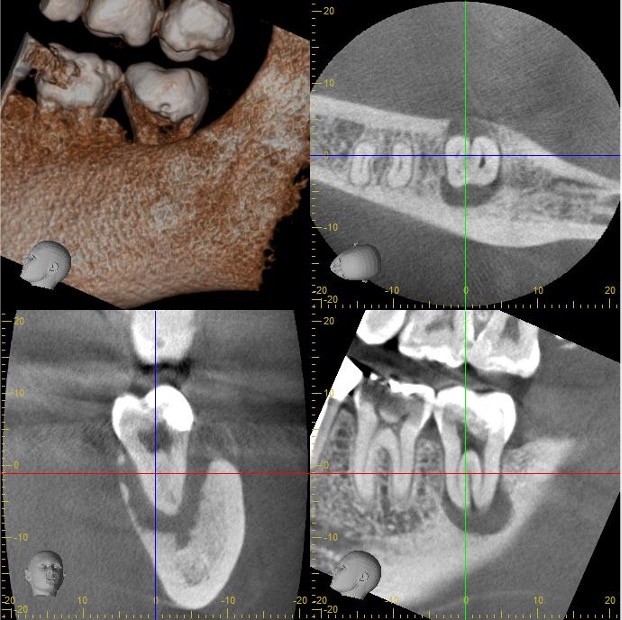

- 治療内容

- 左上第二大臼歯

かかりつけ医より、ご紹介をいただき、根管治療の引き継ぎとなりました。

歯が猛烈に痛くなり、かかりつけ医で診察を受けたところ、歯髄壊死と根尖性歯周炎と診断され、応急処置として大まかな炎症を取り除いてもらいました。

①左上の一番奥の歯で器具が届きにくいこと。 また、治療がテクニックセンシティブな歯であること

②上顎洞と病変が交通していること

などを考慮されて、かかりつけ医の先生より、根管治療専門医での治療を勧められ、ご紹介来院されました。

CT所見では、病変が上顎洞底を突き抜け、上顎洞内への道を作っている状態でした。

治療後3ヶ月後のCT検査では、病変の縮小傾向を認め、上顎洞と病変の交通も遮断され改善されていました。

治癒を確認し、最終補綴は、ご紹介頂いたかかりつけ医で行っていただきました。

- 治療のリスク

- 上顎洞と病変が交通しているため、根管内を洗浄する薬液や、根管充填材などの異物が、上顎洞に入り込まないように、細心の注意を払う必要があった。